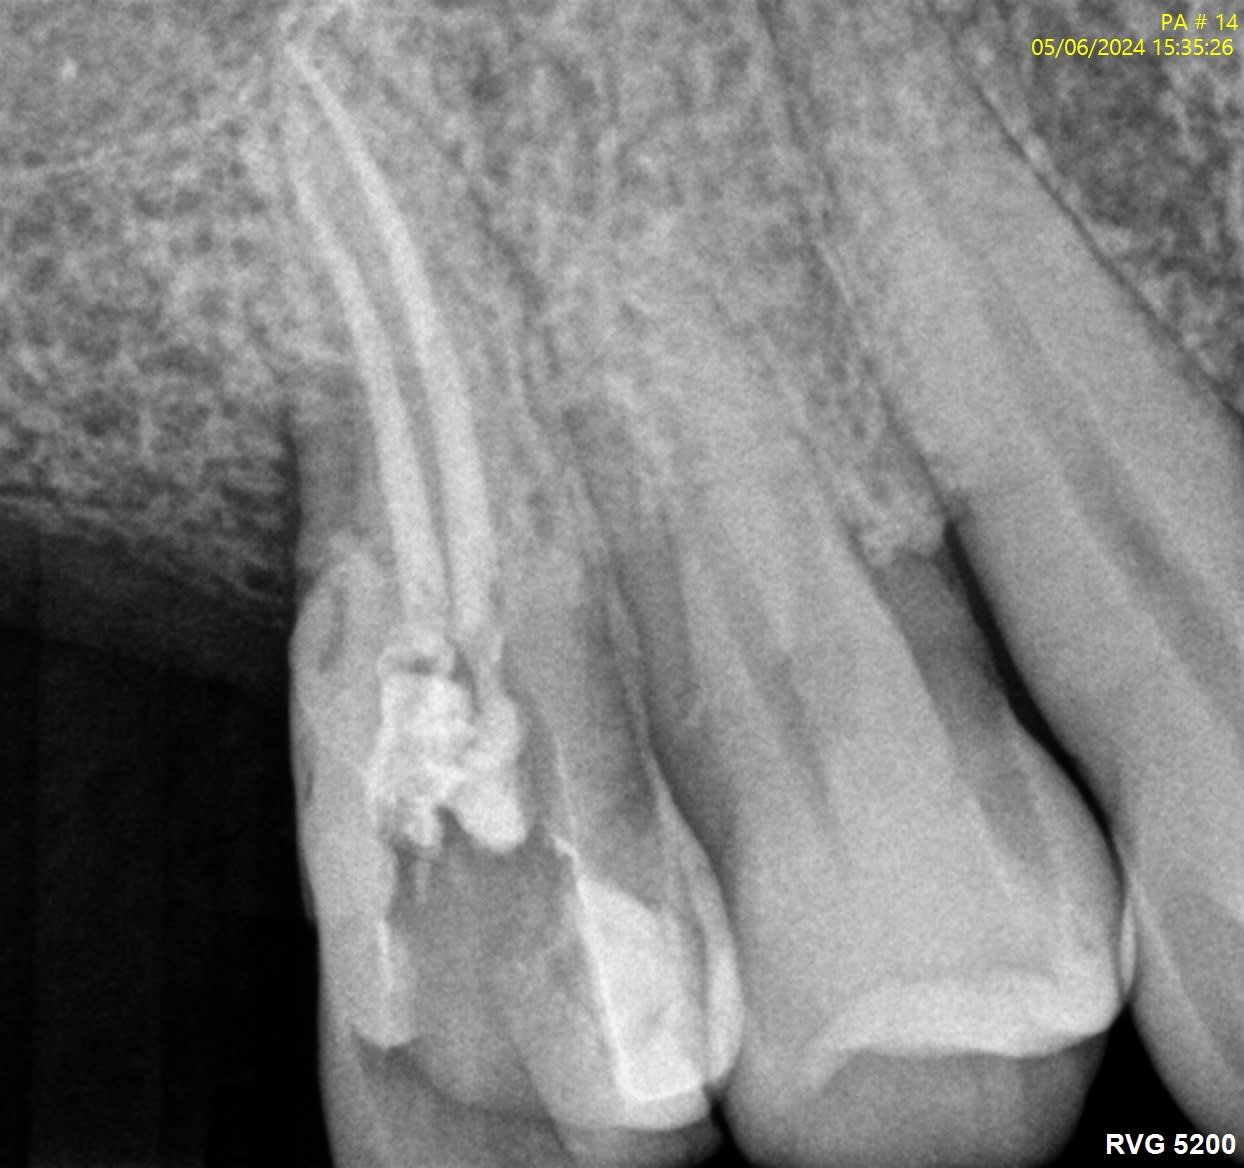

Voici quelques radio pour illustrer...

J’ai l’impression que sur les radios que tu montres il y a des fractures verticales.

La 24 et la 25, t'aurais carrément dû les virer...

> La 24 et la 25, t'aurais carrément dû les virer...

Du tout, c'est joli la zircone, et c'est gratuit.

Sur des endo avec une pulpe saine comme les 24 25, en t'arrêtant à 5 mm, tu auras le même taux de réussite qu'à 0.